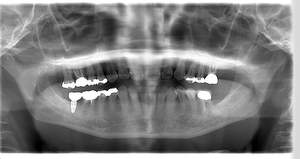

インプラント治療の症例3

レントゲン写真

- Befor

- After

口腔内写真

| 年齢 | 50代・男性 |

|---|---|

| 主訴 | 左下7番 |

| 治療内容 | 右下7番インプラント埋入 |

| 治療費 | 合計:572,000円 診断料:55,000円 埋入料:165,000円 サージカルガイド:55,000円 静脈内鎮静麻酔:77,000円 仮歯:55,000円 上部構造(フルジルコニア):165,000円 (2023年1月現在) |

| 治療期間 | 約8ヶ月 |

| リスク・副作用 | リスク・副作用 |

| 治療方針 | 骨が十分にあるため、骨造成をすることなく埋入した。かみ合わせが強いので、負荷がかからないよう、夜寝るときにマウスピースをつけるよう指示をした。 |

| 担当者所見 | 左下6番7番のインプラントは他院で埋入しており、右下7番は抜歯したままで、かみ合わせの歯が落ちてきてしまうのでインプラントを埋入しました。 |